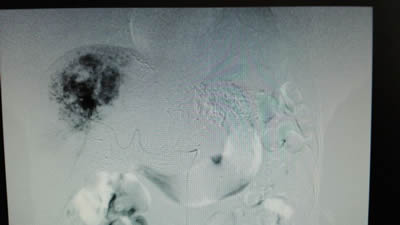

术前影像学发现右肝7×5cm的肝血管瘤 术前影像学发现左肝5×4cm的肝血管瘤

术前:DSA下右肝7×5cm的肝血管瘤成像 术前:DSA下左肝5×4cm的肝血管瘤成像